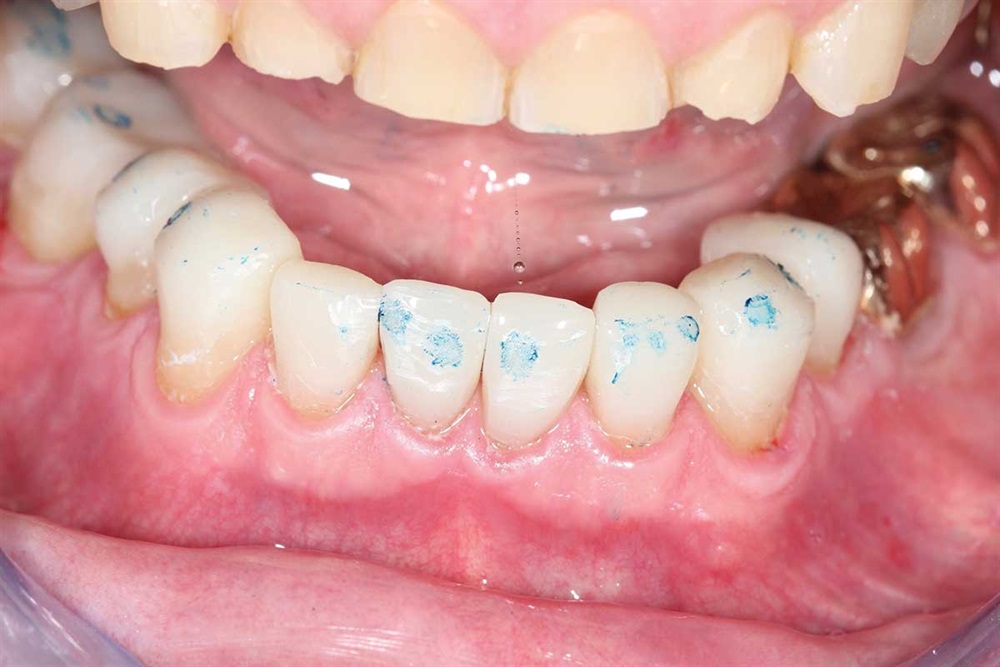

Fig. 11: Got the teeth all hitting with the same pressure. However, I kept the lower central incisors in lighter occlusion because they were worn more than the rest.

Show Your Work